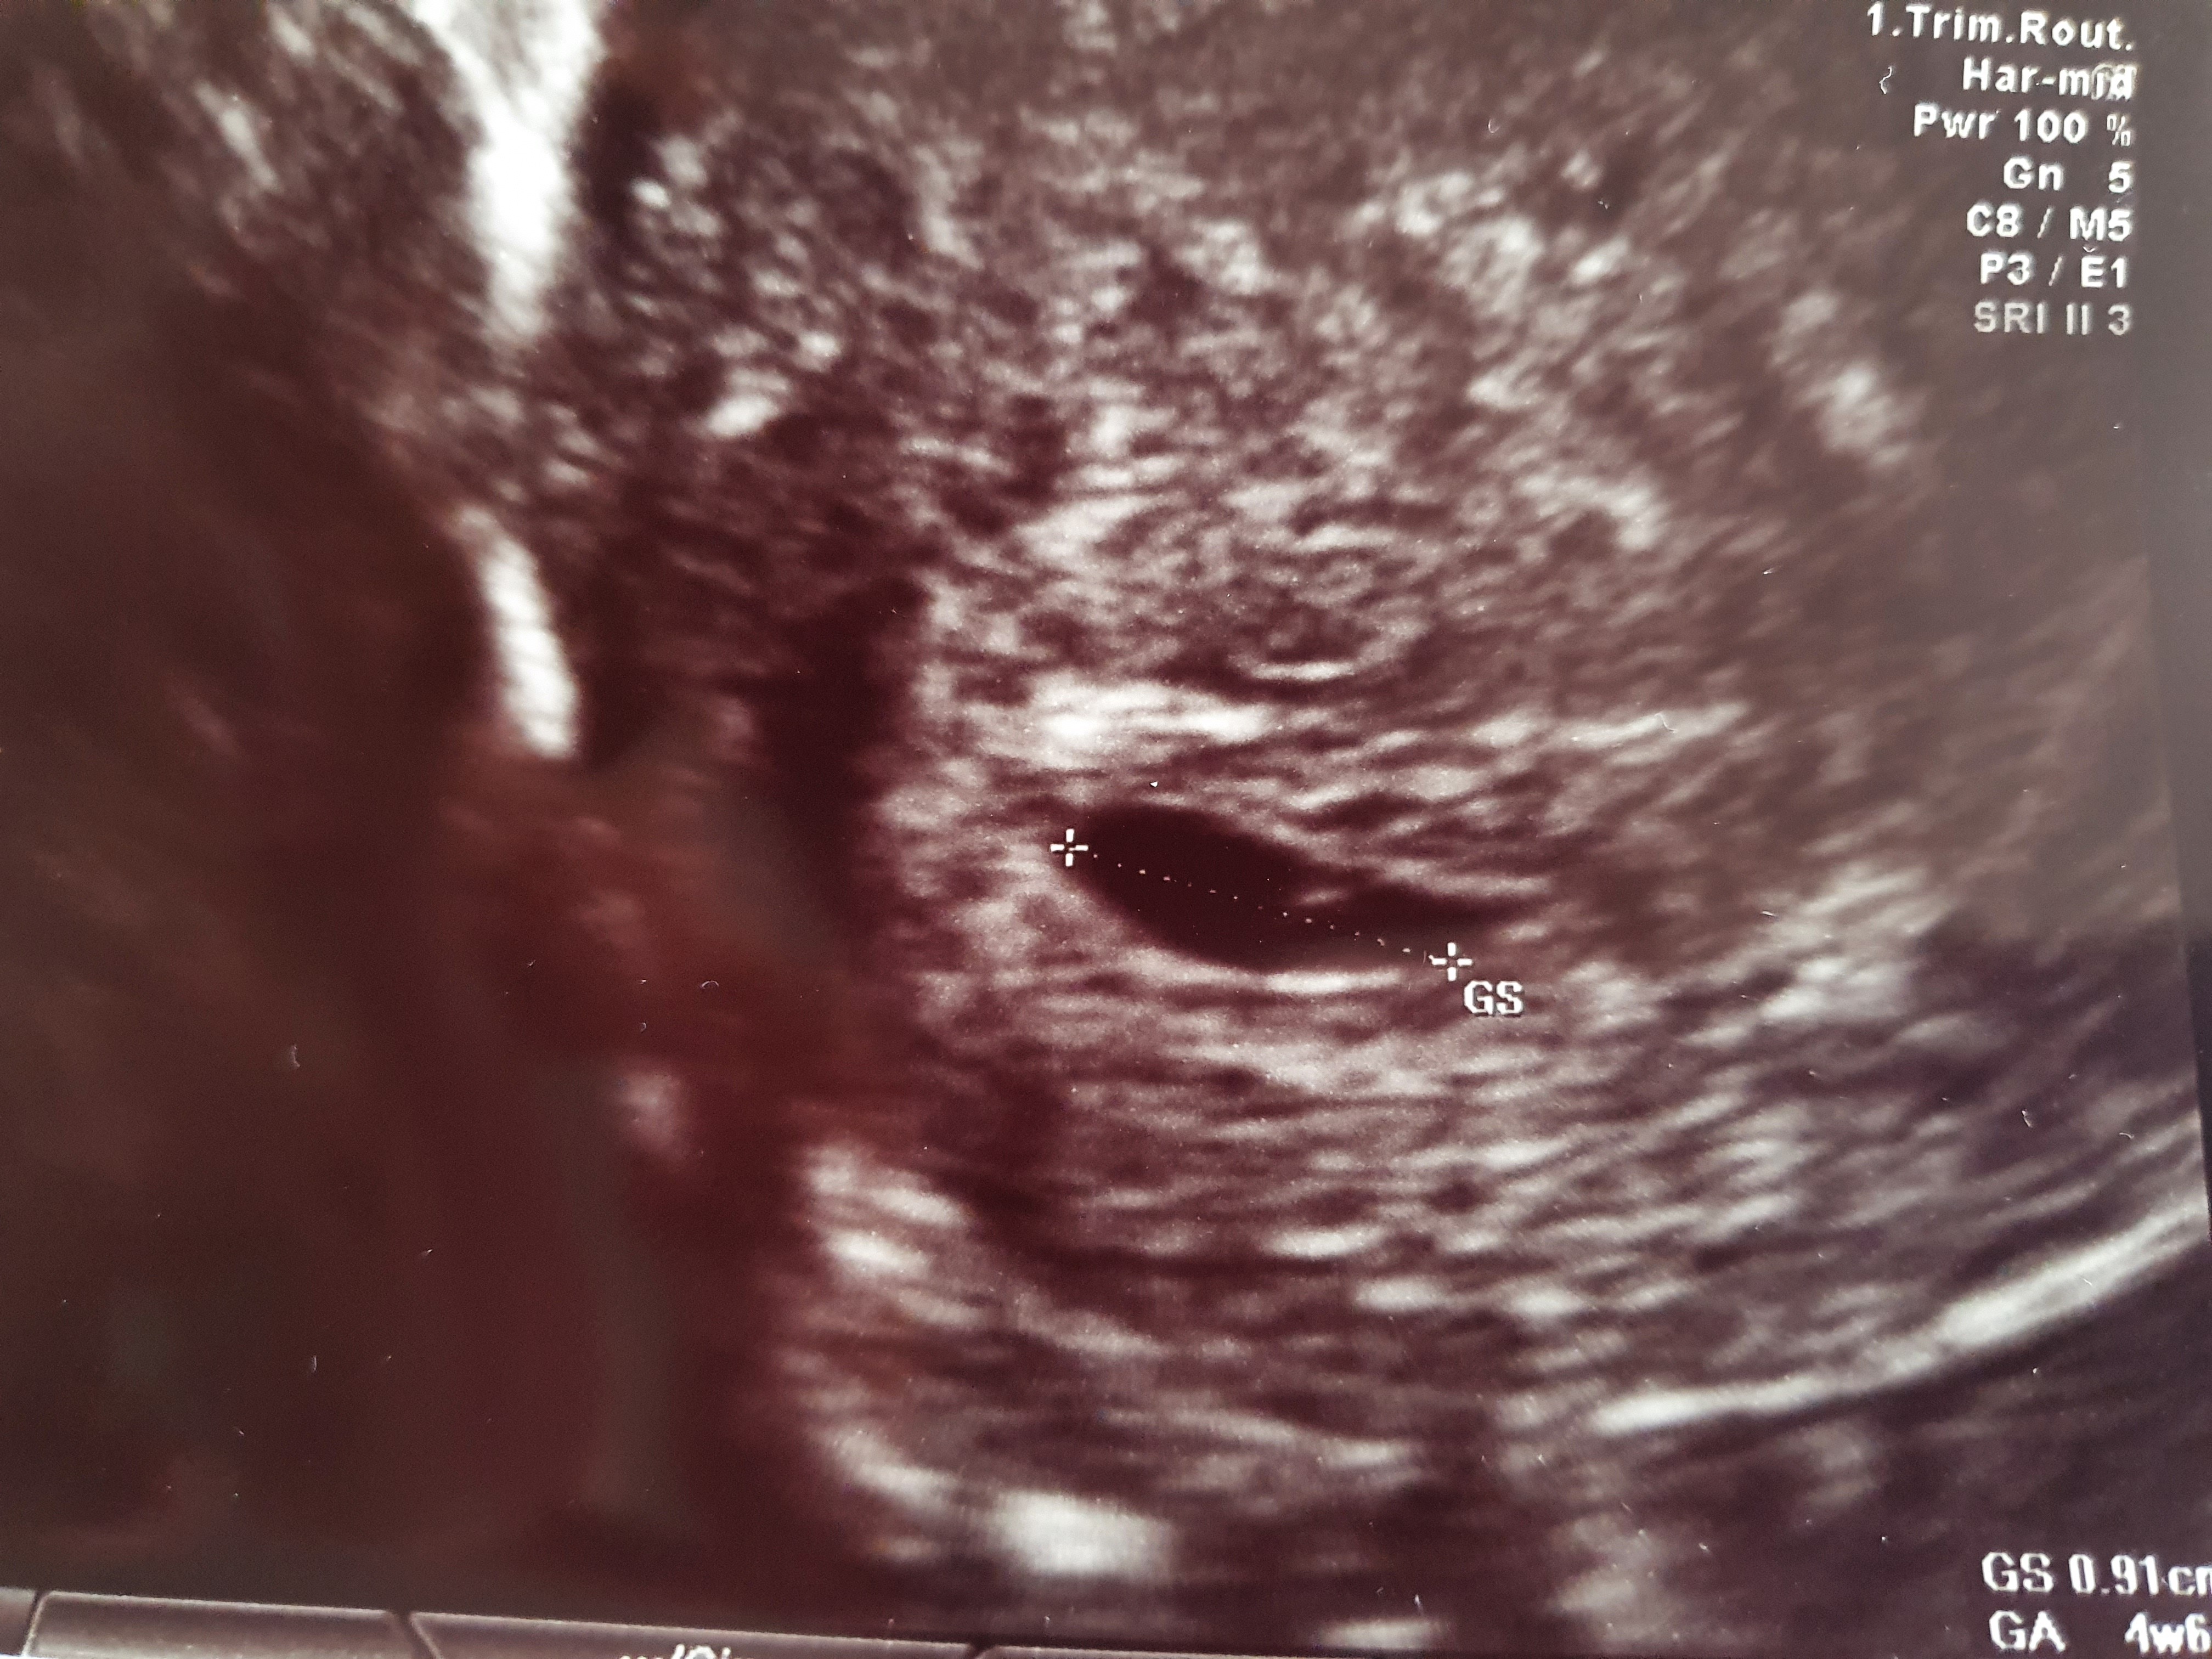

Wróciłam od lekarza, do końca normalnie nie jest. Wg pomiaru 4+6, pęcherzyk jest w macicy, na razie bez zarodka i ciałka żółtego. Za to mam dwie wielkie torbiele, jedna ma wyrzuty krwi, a druga może być pozamaciczną co muszę kontrolować. W razie plamień i silniejszego bólu jajnika mam jechać do szpitala, za tydzień kolejna kontrola, jeśli cysty będą się powiększały położy mnie do szpitala.

Załączniki

• 20210419_125755.jpg

20210419_125755.jpg

1,7 MB · Wyświetleń: 117

• 20210419_130152.jpg

20210419_130152.jpg

2 MB · Wyświetleń: 108

• 20210419_125643.jpg

20210419_125643.jpg

2 MB · Wyświetleń: 102